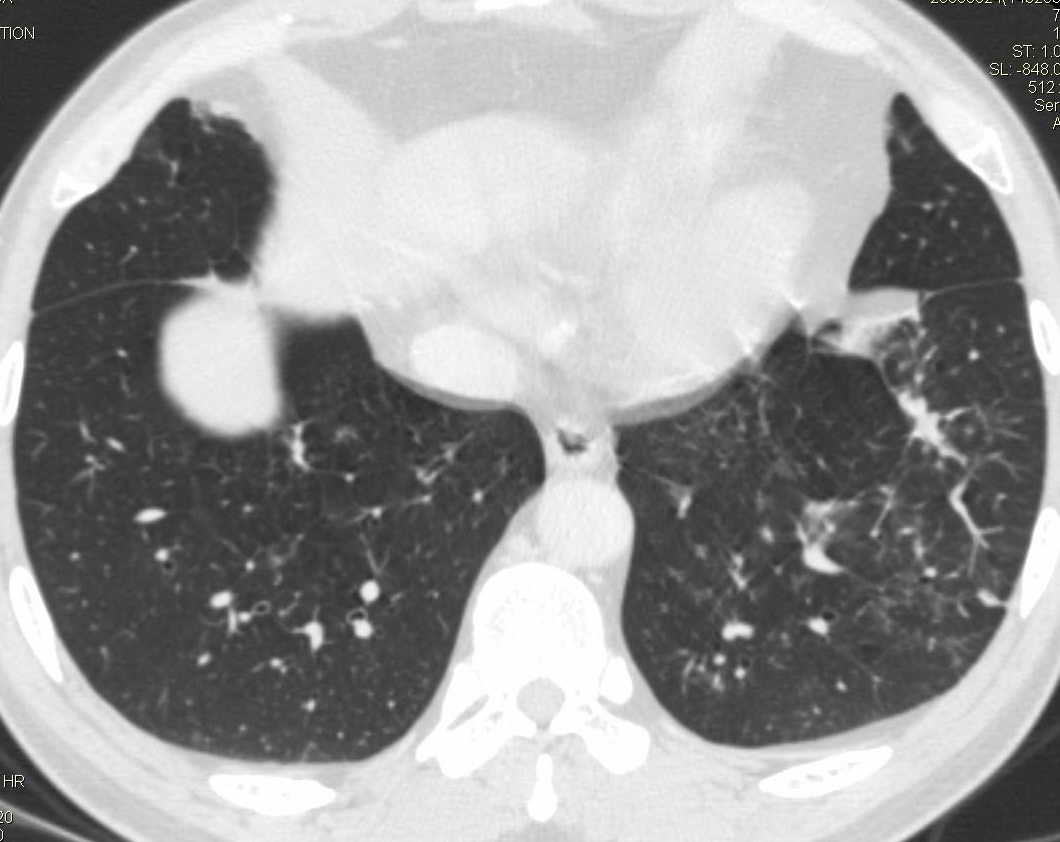

标题: CT15857:男性 58岁 咳痰带血 无发热 请各位大侠发表一下意见 [打印本页]

标题: CT15857:男性 58岁 咳痰带血 无发热 请各位大侠发表一下意见

两肺下叶肺纹理增多、增粗并呈“树芽状”改变。支气管扩张呈囊状,部分呈柱状改变。其周围可见散在的斑片样及条索样密度增高影,右肺下叶近叶间胸膜可见一形态不规则的高密度结节影,并与胸膜粘连。

考虑:支扩并发感染。

双肺多发炎性病灶,结核可能性大,建议抗炎治疗复查.右肺下叶前基底段结节灶,高度警惕肺癌可能

双肺间质性改变(间质纤维化?)伴支扩。右肺下叶有毛刺的小结节,考虑周围型肺癌可能性。